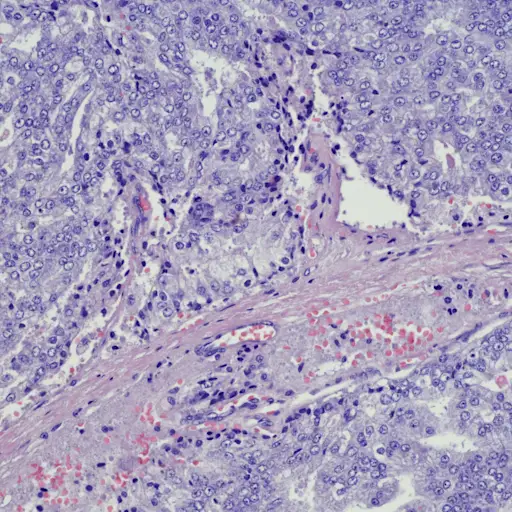

如何测量前列腺癌的分期

在你接受主动监测之前,你的医生需要确定你的癌症已经通过活检和其他工具得到了正确的评估。前列腺癌专家Edmund Folefac M.B./ c.h.b说:“你要确定你没有错过更严重癌症的区域。他是哥伦布俄亥俄州立大学(The James, Ohio State University)综合癌症中心的医学肿瘤学家。如果你的Gleason评分(前列腺癌的标准评分)是6分(癌症的最低等级),或者在某些情况下是7分,你可能会开始积极监测。